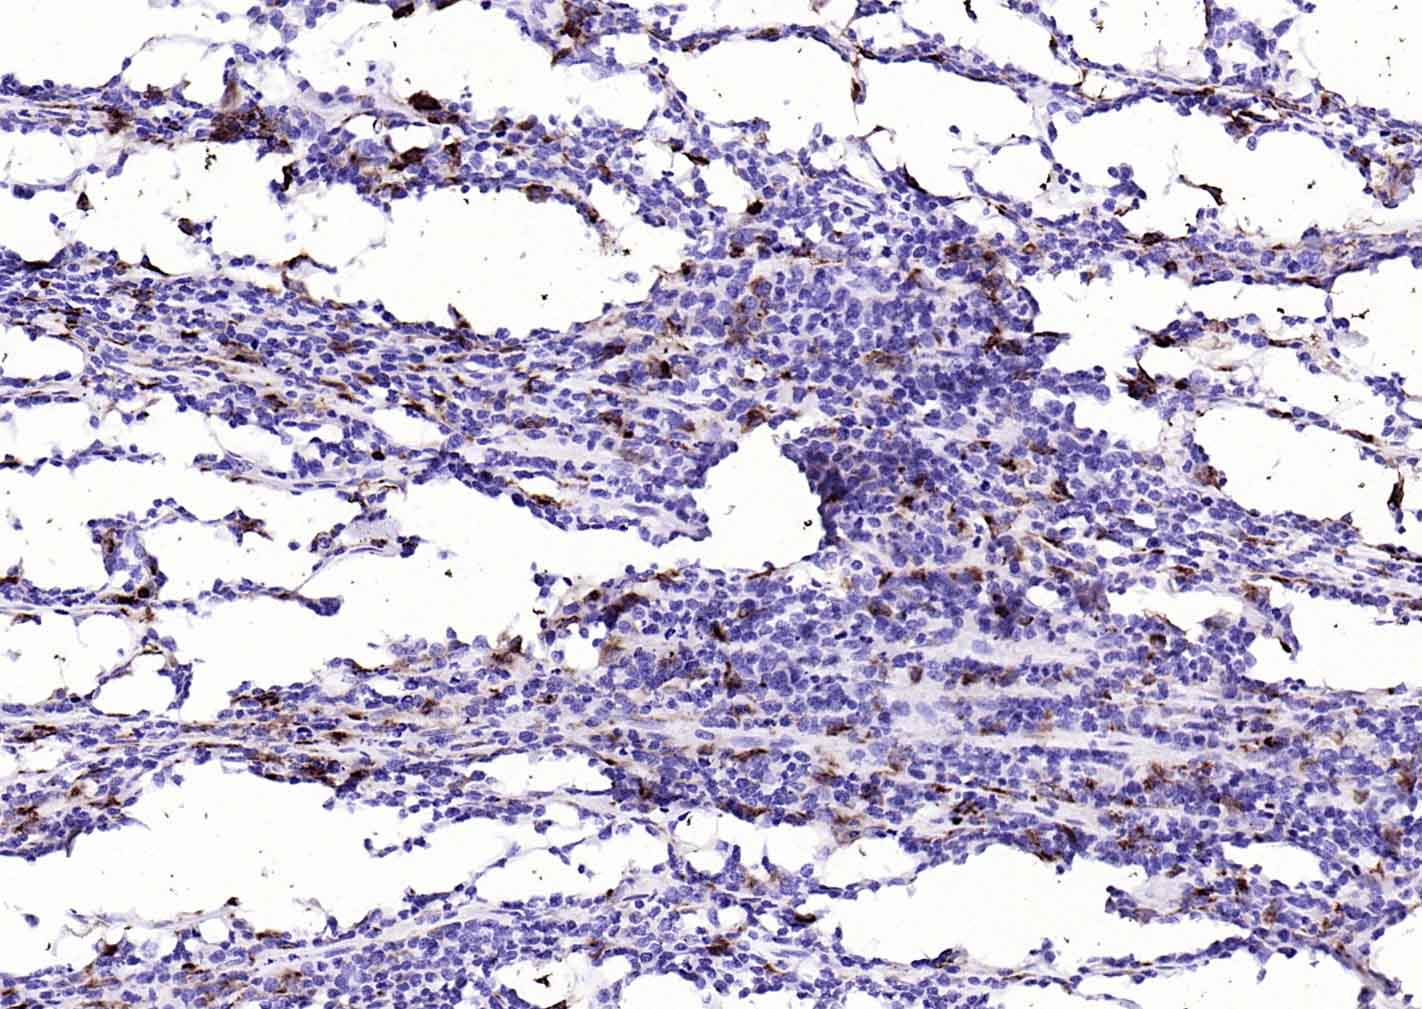

| 英文名称 | CD68 Mouse mAb |

| 中文名称 | CD68单克隆抗体 |

| 产品应用 | IHC-P=1:50-200, IHC-F=1:50-200, IF=1:50-200 Not yet tested in other applications. |

| 交叉反应 | Human, Rat, spleen, spleen, spleen, spleen, human lung carcinoma, human lung carcinoma, human lung carcinoma, human lung carcinoma, lymphoid, lymphoid, lymphoid, lymphoid, human tonsil, human tonsil, human tonsil, human tonsil, 肝, 肝, 肝, 肝, spleen, spleen, spleen, Human diffuse large B-cell lymphoma, Human diffuse large B-cell lymphoma, Human diffuse large B-cell lymphoma, Human diffuse large B-cell lymphoma |

| 组织特异性 | Highly expressed by blood monocytes and tissue macrophages. Also expressed in lymphocytes, fibroblasts and endothelial cells. Expressed in many tumor cell lines which could allow them to attach to selectins on vascular endothelium, facilitating their dissemination to secondary sites. |

| 功能 | Could play a role in phagocytic activities of tissue macrophages, both in intracellular lysosomal metabolism and extracellular cell-cell and cell-pathogen interactions. Binds to tissue- and organ-specific lectins or selectins, allowing homing of macrophage subsets to particular sites. Rapid recirculation of CD68 from endosomes and lysosomes to the plasma membrane may allow macrophages to crawl over selectin-bearing substrates or other cells. |

| 背景资料 | This gene encodes a 110-kD transmembrane glycoprotein that is highly expressed by human monocytes and tissue macrophages. It is a member of the lysosomal/endosomal-associated membrane glycoprotein (LAMP) family. The protein primarily localizes to lysosomes and endosomes with a smaller fraction circulating to the cell surface. It is a type I integral membrane protein with a heavily glycosylated extracellular domain and binds to tissue- and organ-specific lectins or selectins. The protein is also a member of the scavenger receptor family. Scavenger receptors typically function to clear cellular debris, promote phagocytosis, and mediate the recruitment and activation of macrophages. Alternative splicing results in multiple transcripts encoding different isoforms. [provided by RefSeq, Jul 2008] |